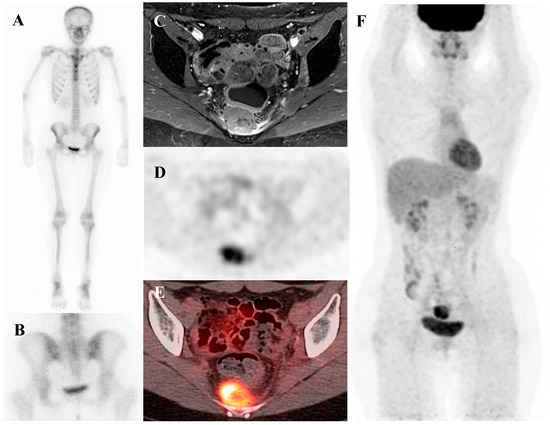

Current Position of Nuclear Medicine Imaging in Primary Bone Tumors

Primary bone tumors encompass a heterogeneous spectrum ranging from benign entities to highly aggressive sarcomas. This review aims to summarize the current role and future perspectives of nuclear medicine in the diagnosis, staging, and management of primary bone tumors. Accurate diagnosis and staging [...] Read more.

Primary bone tumors encompass a heterogeneous spectrum ranging from benign entities to highly aggressive sarcomas. This review aims to summarize the current role and future perspectives of nuclear medicine in the diagnosis, staging, and management of primary bone tumors. Accurate diagnosis and staging are critical yet challenging due to histologic heterogeneity and overlapping imaging features. While radiographs, computed tomography (CT), and magnetic resonance imaging (MRI) remain essential, nuclear medicine provides a complementary functional perspective by assessing bone turnover, vascularity, and glucose metabolism. Bone scintigraphy is highly sensitive for skeletal lesions and useful for detecting skip lesions or multifocal disease, although its specificity is limited. Hybrid single-photon emission computed tomography (SPECT)/CT enhances diagnostic confidence through precise anatomic localization and quantitation. [18F]fluorodeoxyglucose ([18F]FDG) positron emission tomography (PET)/CT, by directly visualizing tumor metabolism, has become a cornerstone in osteosarcoma and Ewing sarcoma management, demonstrating superiority over bone scintigraphy for detecting skeletal metastases. In chondrosarcoma, [18F]FDG uptake correlates with histologic grade, although overlap with benign cartilage tumors complicates interpretation. Future directions include the integration of quantitative SPECT, artificial intelligence, and novel tracers such as [18F]sodium fluoride and [68Ga]Ga-fibroblast activation protein inhibitor (FAPI). Collectively, nuclear medicine imaging is becoming a key element in musculoskeletal oncology, offering unique biological insights that complement anatomic imaging and contribute to improved patient management. Full article

Show Figures

Figure 1